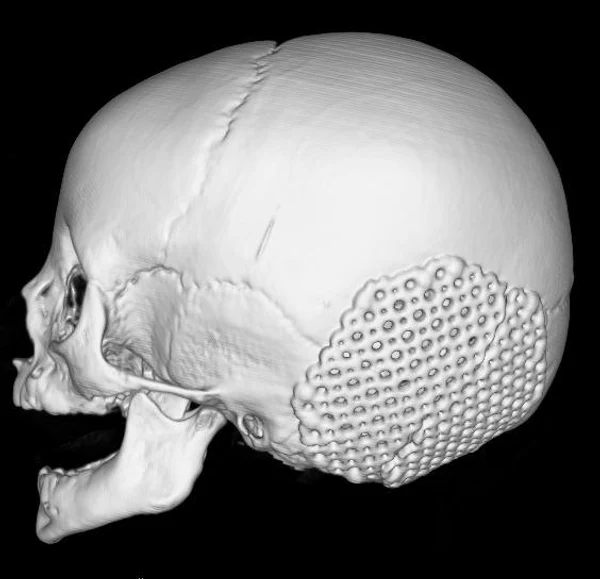

Удаление опухолей черепаВ качестве примера лечения пациентов с опухолями черепа привожу личное наблюдение пациента грудного возраста с опухолью черепа. В возрасте 1 мес. у ребёнка в затылочной области слева родителями обнаружено плотное образование диаметром 5 мм. За 3 мес. до госпитализации образование значительно увеличилось в размерах. При поступлении в возрасте 6 мес. в затылочной области слева (в проекции лямбдовидного шва) имеется безболезненное, плотное, неподвижное, бугристое образование размерами 5 х 4 х 2 см. При КТ и МРТ головы выявлена опухоль черепа в области астериона слева, обладающая преимущественно интракраниальным ростом (рис. 30 а). Ребёнку выполнено удаление опухоли черепа (рис. 30 б). Образовавшийся дефект черепа больших размеров закрыт перфорированной титановой пластиной (рис. 30 в). При наблюдении пациента в течении 2-х лет рецидива заболевания и деформации черепа не отмечалось.